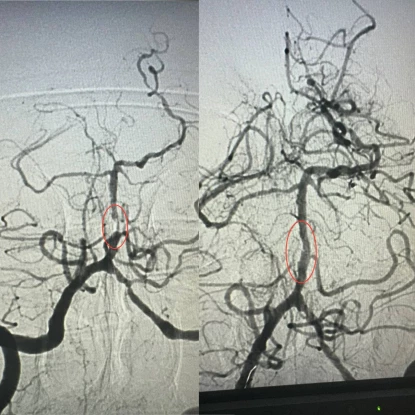

По словам заведующего рентгенэндоваскулярным блоком больницы Александра Скрипки, речь шла о крайне опасном поражении — инсульте стволовой части мозга. Базилярная артерия была почти полностью заблокирована атеросклеротической бляшкой, что создавало серьезную угрозу жизни.

Медики приняли решение провести ангиопластику пораженной артерии. Хотя больница имеет опыт такого вмешательства в кардиологии при атеросклерозе коронарных сосудов, но применение методики к мозговым артериям является новаторским подходом для украинской медицины.